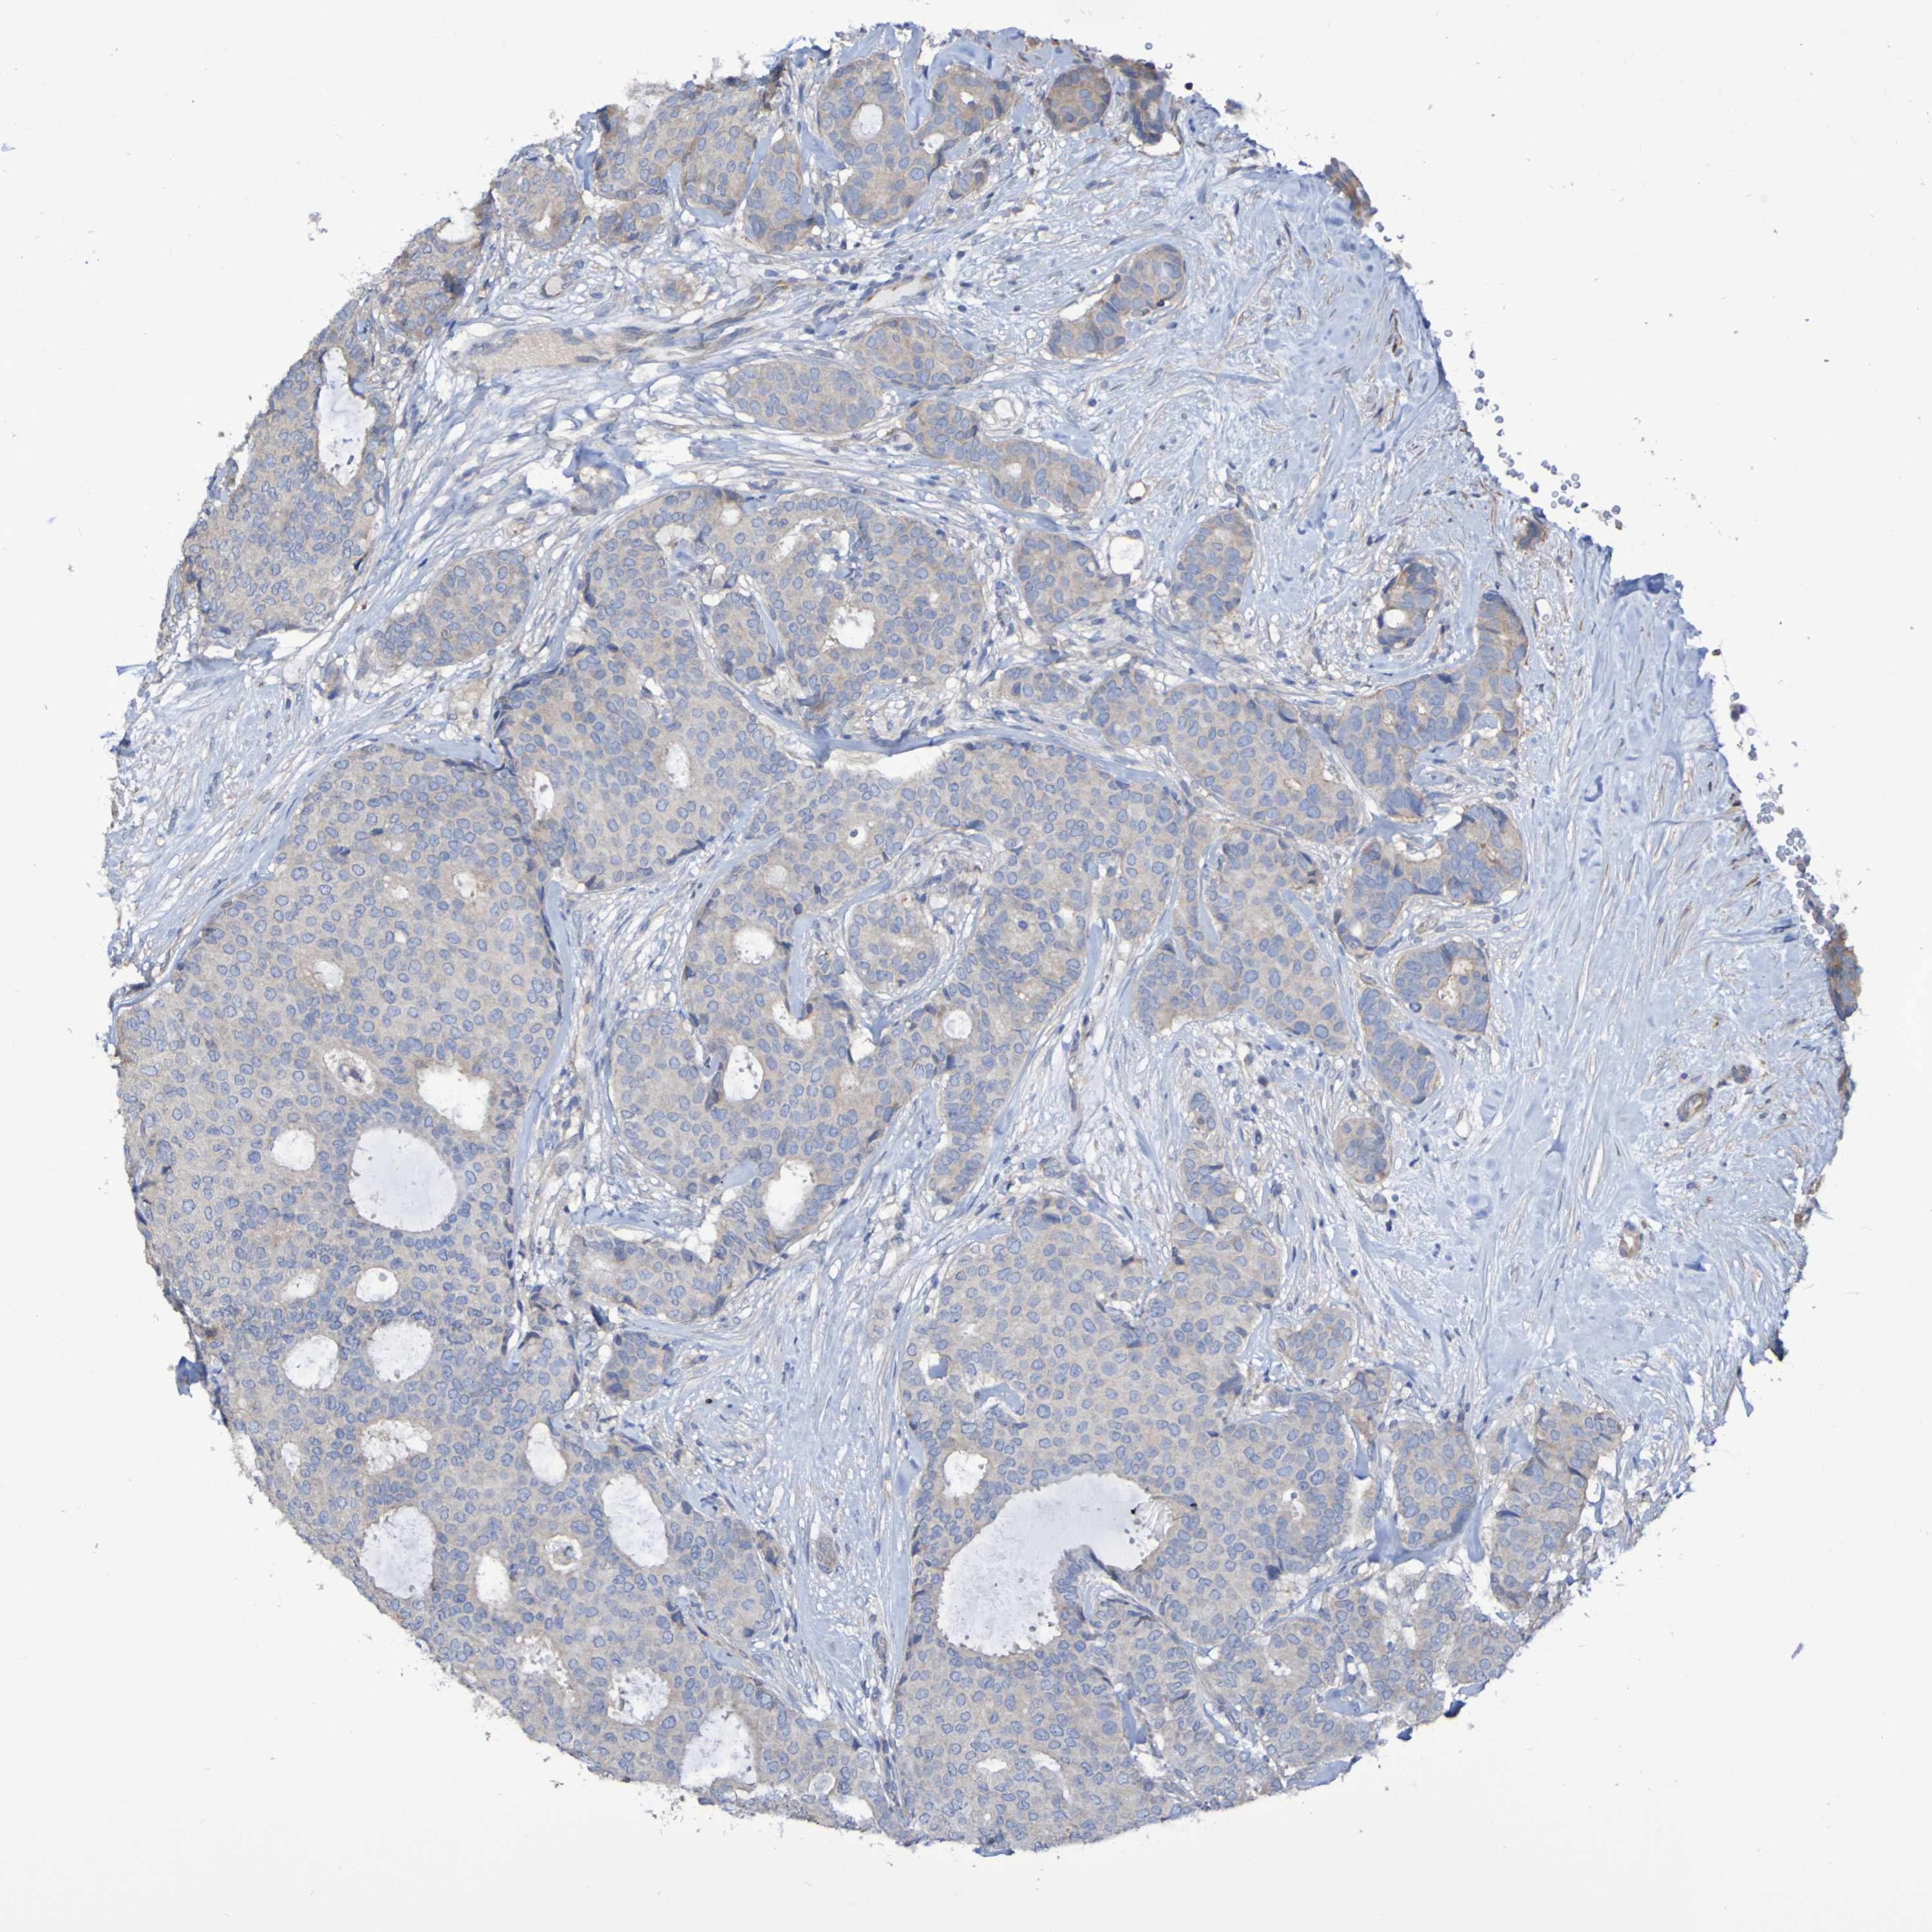

CANCER BREAST CANCER Show tissue menu

BRCA TCGA BRCA VALIDATION PROTEIN EXPRESSION

Breast cancer

Human cancer